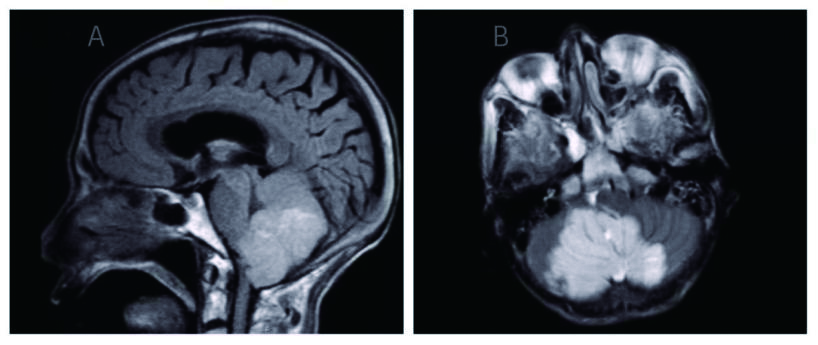

1 资料与方法患者男,70岁,农民,入院前3 d受凉后出现咳嗽,为阵发性干咳、无痰,伴胸闷、气喘,平卧及活动时加重,发热,体温最高37.7 ℃,热型未监测,无畏冷、寒战;当地医院胸部X线平片示左侧胸腔积液、左侧肺炎,予以“头孢噻肟”抗感染治疗无效,于2015年9月29日转来厦门大学附属第一医院。既往慢性支气管炎病史20余年,吸烟史50年×40支/d。入院时查体:T 37.6 ℃,P 106次/min,R 26次/min,BP 118/72 mmHg,SPO2 91%,神志清楚,反应迟钝,有时答非所问,呼吸较急促,气管轻度右偏;左侧胸部呼吸运动减弱,语颤消失,叩诊呈浊音,呼吸音减弱,右肺散在哮鸣音;心界不清,心率106次/min,节律规整,各瓣膜区未闻及杂音。入院后观察患者热型为不规则低热,查血尿粪常规、肝肾功能、肿瘤标志物等正常,降钙素原0.826 ng/mL,结核抗体及结核菌素实验阴性。血气分析:氧分压6.63 kPa,二氧化碳分压正常,无酸碱失衡表现。胸部CT示,双肺多发感染,左侧大量胸腔积液;右肺局限性肺大泡,肺气肿(图 1)。入院后给予莫西沙星抗感染,胸腔穿刺引流出大量淡红色稍混浊胸水,无臭味,每日引流量300~600 mL;胸水常规:李凡他试验阳性,蛋白48.6 g/L,有核细胞数1 520×106/L,比重1.021。患者仍有反复低热,热峰及持续时间稍改善。入院后10 d胸水培养结果回报为星型奴卡菌感染(图 3、4),抗生素更换为TMP-SMX 0.96 g/12 h联合红霉素0.25 g/8 h治疗,体温逐渐下降至正常,咳嗽、气喘症状缓解,胸水引流量逐渐减少至消失,PCT和血气分析结果恢复正常,胸部CT:左侧少量胸腔积液,伴积气(图 2)。于2015年10月25日出院,继续口服TMP-SMX片及红霉素片治疗,定期随诊。患者感觉恢复良好在出院后1个月左右自行停药,3个月后因右侧肢体无力再诊我院,颅脑MRI提示:大面积小脑梗死,脑疝并幕上脑积水(图 5),再诊时未再复查胸部CT,2 d后因呼吸循环衰竭死亡,家属未同意尸检。

| 图 5 大面积小脑梗死伴脑疝形成(A:矢状面; B:水平面) |

本例患者胸水中培养出星型奴卡菌,属比较常见的肺奴卡菌病,使用TMP-SMX+红霉素后病情得到明显好转,过早停药后因脑梗死并发脑疝死亡,虽然未行尸检不明确脑梗死栓子来源,但考虑一方面奴卡菌病可于中枢神经系统原发或者经由血流播散至中枢神经系统,在脑部形成化脓性病变如脑脓肿或者脑膜炎[19]。另一方面,近年来有学者提出感染性脑卒中的概念,指出慢性感染存在感染负荷,为卒中发生危险因素[20],其机制可能与感染后出现全身炎症反应亢进及免疫功能抑制[21-22],随之引起的高凝状态、血小板激活、血管内皮损伤等相关[23],但目前仍未见明确奴卡菌所致感染诱发脑梗死的报道。本例患者首次住院时就存在“反应迟钝、答非所问”等症状,由于认识不足而忽略了搜集奴卡菌中枢神经系统受累的证据;故本例脑梗死与奴卡菌病之间存在相关联的可能性较大,遗憾的是本例患者并没有得到直接证据。